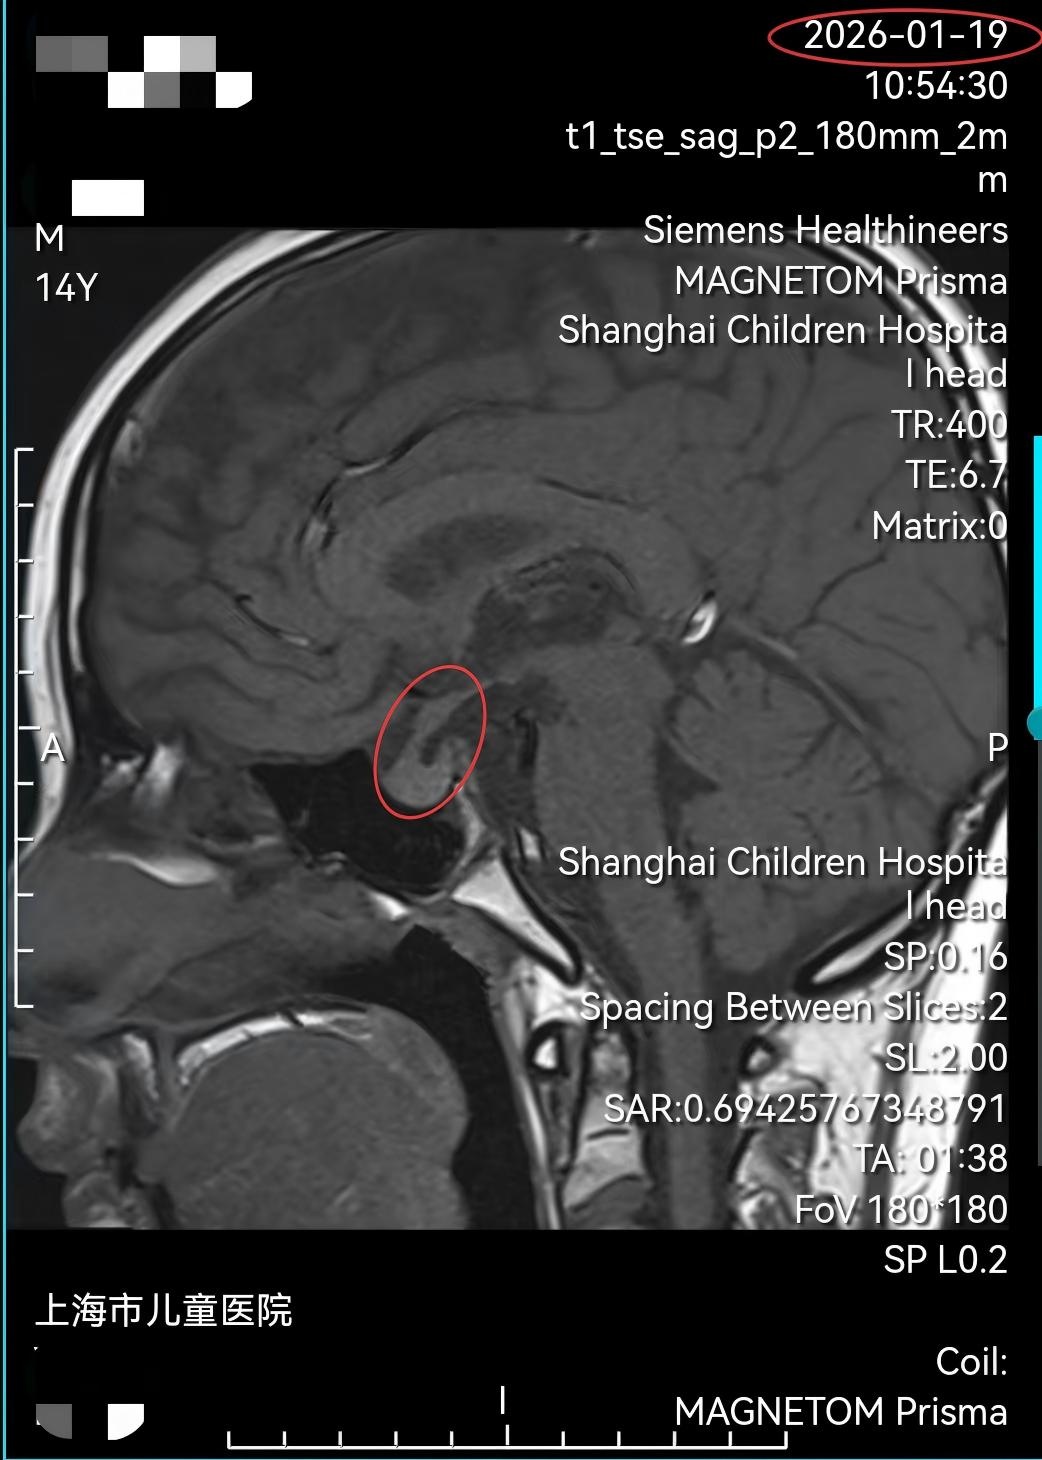

结合细致的影像学判读与多学科综合研判,专家们一致明确诊断为“鞍区生殖细胞瘤伴出血”。面对这一深藏于生命中枢、已局部侵袭关键结构的肿瘤,若采用传统开颅手术,不仅创伤大、风险极高,还会对垂体功能造成不可逆的影响。经过反复论证与审慎评估,在郭盛的牵头下,MDT团队最终形成共识:优先采用对生殖细胞瘤高度敏感、且能最大限度保护患儿神经内分泌功能的化疗方案,作为此次治疗的首选策略。

在严密监护下,小易接受了针对性的化疗。令所有人惊喜的是,仅仅3天后复查磁共振(MRI)显示,鞍区的肿瘤病灶已基本消失,之前被肿瘤压迫的垂体得以显露。小易持续多年的剧烈头痛症状完全消失,原本无法睁开的左眼也灵活自如,精神状态大为好转。